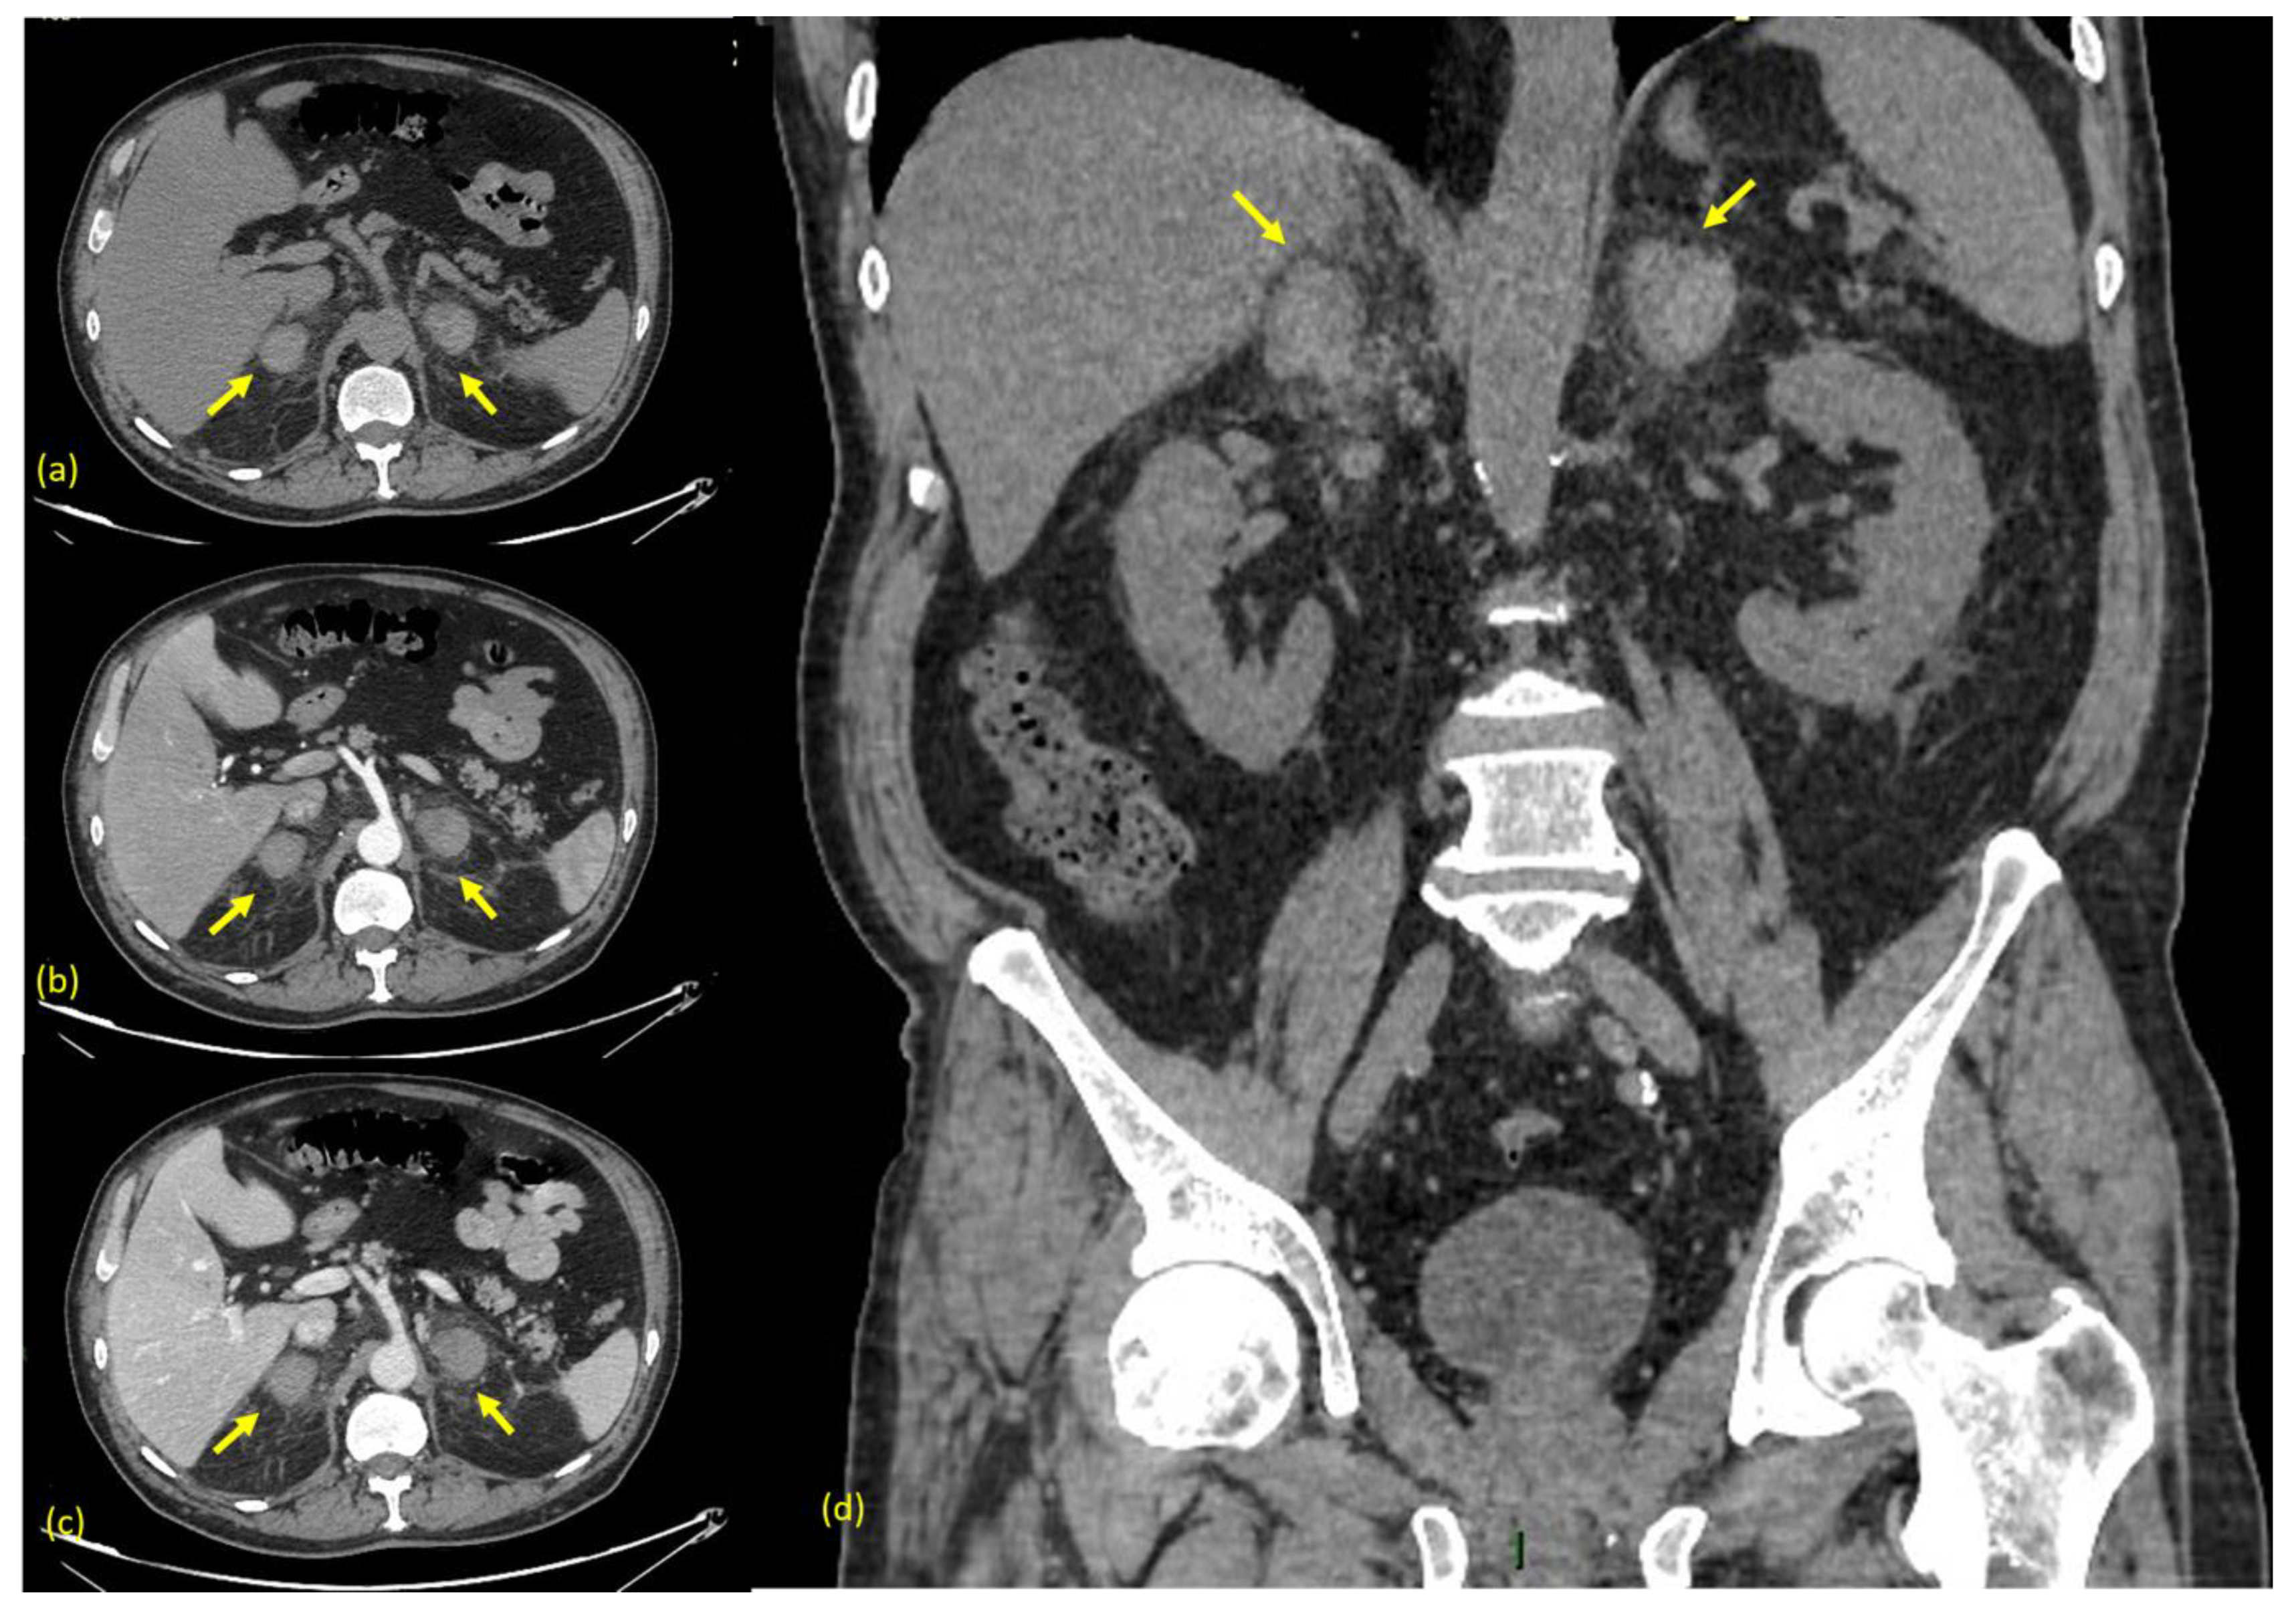

Therefore, he was immediately subjected to a computed tomography (CT) scan of the abdomen before and after the administration of contrast medium (Omnipaque 350 mgI/mL, 130 mL, 3 mL/s), with a 1.25 mm slice width, 120 kV, and 7 mAs. The non-contrast phase demonstrated slightly hyperdense round masses with fuzzy margins and a diffuse swelling of both adrenal glands, associated with inflammatory changes in the surrounding retroperitoneal fat, confirming the presence of a bilateral adrenal hemorrhage (Figure 2a). After the intravenous contrast, no enhancement was revealed (with density values of 45–55 HU both in pre-contrast and post-contrast phases) and no ”blushes” were revealed, suggesting no evidence of active bleeding (Figure 2b–d).

Figure 2.

(a) CT axial non-contrast phase. (b) CT axial post-contrast arterial phase. (c) CT axial post-contrast portal venous phase. (d) CT coronal non-contrast phase. Arrows indicate the adrenal glands. The non-contrast phase demonstrates slightly hyperdense round masses with fuzzy margins and diffuse swelling in both adrenal glands, in association with inflammatory changes in the surrounding retroperitoneal fat, which is strongly suggestive of bilateral adrenal hemorrhage. After the intravenous contrast, no contrast blushes are shown, suggesting no evidence of active bleeding.

If clinically suspected, an urgent CT scan of the abdomen is strongly suggested as the “gold standard” in the diagnosis of adrenal hemorrhage. It usually shows adrenal hematomas that characteristically appear round or oval, often with surrounding strandings of the periadrenal fat. In rare cases, if arterial active bleeding is occurring, a post-contrast blush might be also detected [15,16]. A condition named “adrenal congestion”, which consists in thickening of adrenal glands and the stranding of the periadrenal fat, can be occasionally detected before the hemorrhage [17]. When clinical and laboratory findings are non-specific, as they were in our case, the CT scan may be preceded by a US scan, which can show an increased volume of both the adrenal glands with diffuse or inhomogeneous echogenicity due to the presence of hematomas [18].

Computed Tomography (CT) is the most important tool in the diagnosis of adrenal bleeding. Adrenal hematomas can typically be detected in the non-contrast phase, where they appear as round to ovoid lesions, usually associated with periadrenal fat stranding and, sometimes, the involvement of the peri-nephric space. The acquisition of post-contrast phases (arterial, venous, and excretory) is crucial to detect any presence of active bleeding, seen as an arterial “blush” [15].

As for the CT density values of an adrenal hematoma, they depend on its stage. In the acute stage, a hematoma usually contains high attenuation areas (between 50 and 90 HU); as time goes on, its size and attenuation values decrease and, in some cases, a complete resolution can be seen.

The typical appearance of a chronic hematoma is a hypodense mass with internal calcifications [16]. An “adrenal congestion”, which consists in the thickening of the adrenal glands and stranding of the periadrenal fat, can be occasionally detected before the hemorrhage [17].